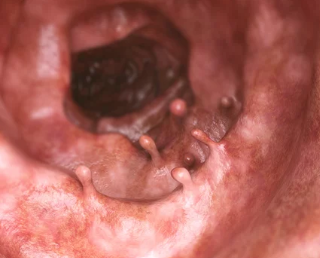

선종과 용종은 대장내시경을 통해 주로 진단됩니다. 진단 이후에는 크기와 성질에 따라 적절한 치료가 진행됩니다.

- 대장내시경: 용종 및 선종을 직접 관찰하고, 필요시 즉시 제거할 수 있는 가장 효과적인 진단 및 치료 방법입니다.